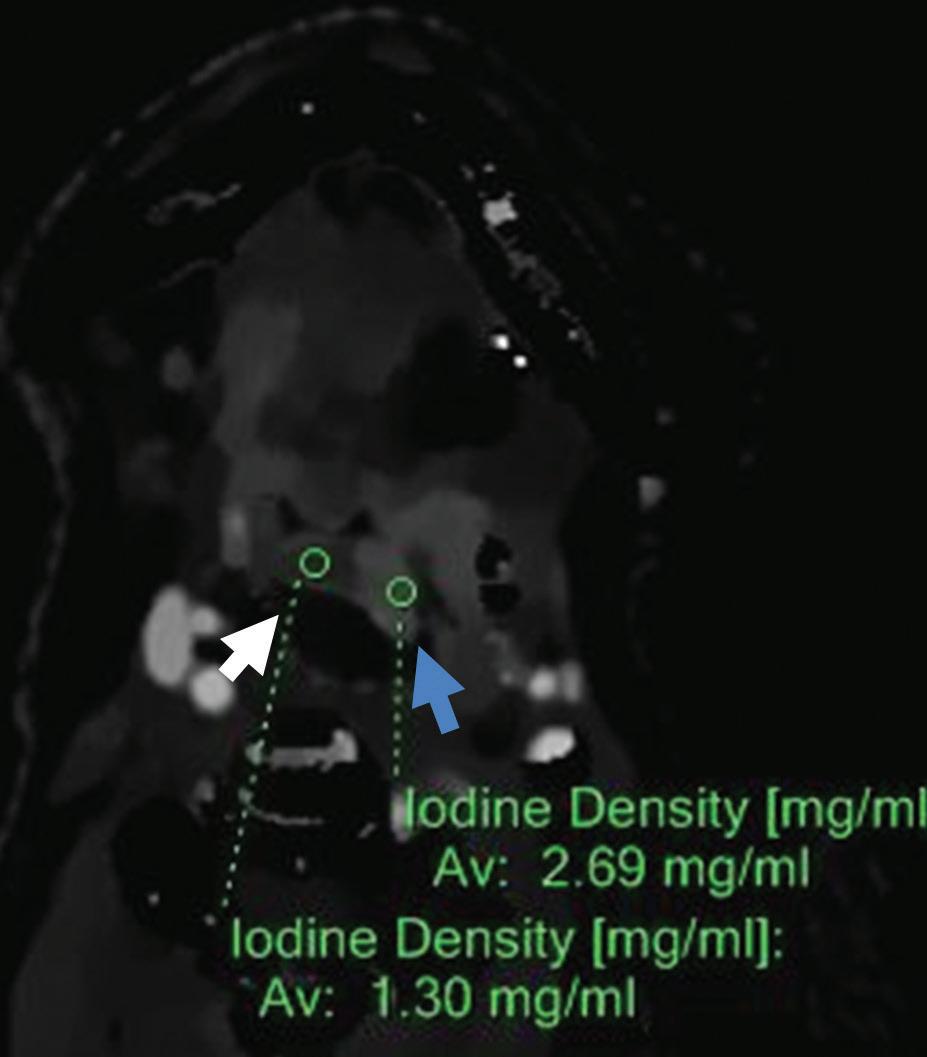

Iodine density image: increased iodine content of the right-sided mass of the tongue (3.05 mg/ml, blue arrow) compared to left side (1.30 mg/ml, white arrow) and increased iodine content of the left submandibular lymph node (1.90 mg/ml).

Iodine density axial image: increased iodine content of the left-sided oropharyngeal infiltration (2.69 mg/ml, blue arrow) compared to right side of oropharynx (1.30 mg/ml, white arrow).

Z effective axial image: left side of oropharynx (blue arrow) with increased iodine content is color coded in dark blue and has higher effective atomic number (8.95) compared to right side of oropharynx (8.20) color coded in light blue-green (white arrow).